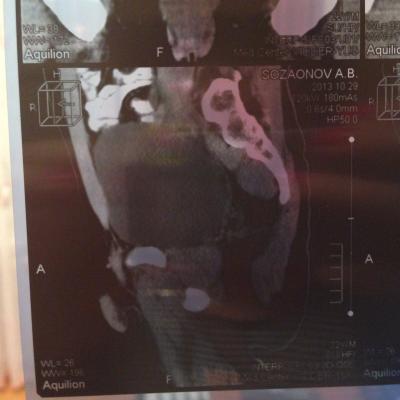

проведена МСКТ области таза!Внеорганных дополнительных патологических образований,лимфаденопатии или свободной жидкости в области таза не выявлено.

Семенные пузырьки-конфигурация не совсем типична,примерный размер правого 26*28мм.Отмечаются признаки кистовидной трансформации и микрокальцинации обоих пузырьков.Наибольшая из кист слева достигает 9 мм.Обращает на себя внимание неравномерная кальцинация стенок крупных регионарных(текстикулярных)артерий с обоих сторон.

Заключение:на момент исследования,КТ-данных за наличие внеорганных дополнительных патологических образований,лимфоденопатии или свободной жидкости в области таза не выявлено.КТ-признаки в пользу проявлений калькулезного везикулита с элементами кистовидной трансформации семенных пузырьков.